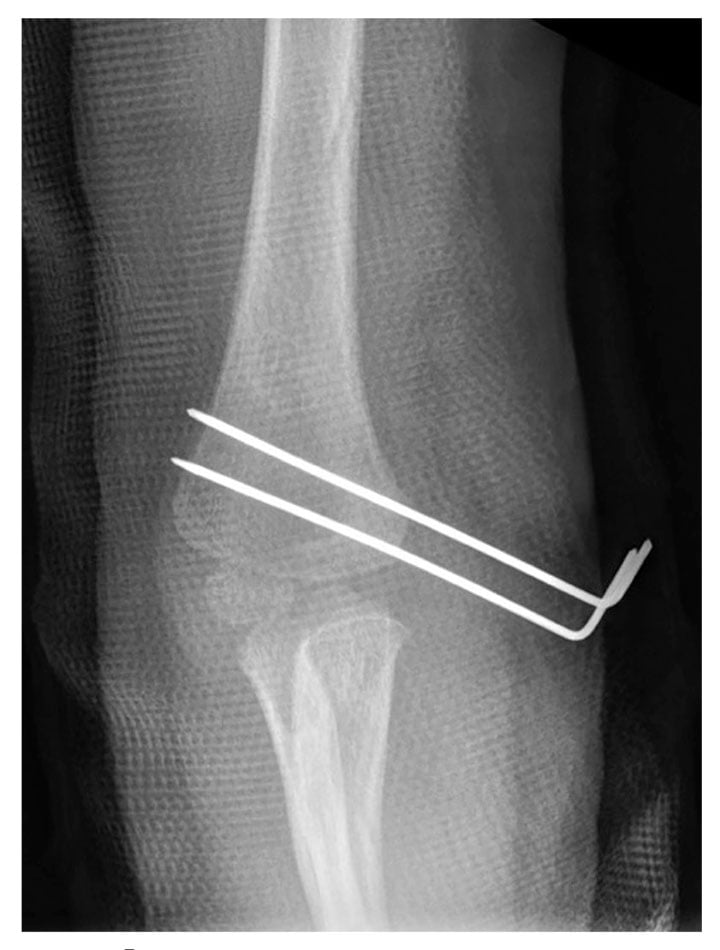

Fractures of the elbow are a common injury in children. Supracondylar humeral fractures are the most prevalent type of elbow fracture, whereas lateral condyle fractures are less common, and medial epicondyle are the least common.1 In children, medial epicondyle ossification occurs between ages 3 and 7 years.2 When a pediatric patient presents with elbow pain and decreased range of motion, a radiographic examination commonly is performed. However, because elbow fractures involving the unossified distal humerus might not be evident using this modality, other imaging examinations, such as magnetic resonance (MR) imaging, should be performed whenever a fracture is suspected. MR imaging can detect bone fractures as well as injury to surrounding anatomy such as cartilage, tendons, and ligaments. This case summary discusses a 2-year-old patient with a fracture of the distal humerus where the unossified cartilaginous trochlear and medial epicondyle fracture fragment was displaced from the joint. (see Figure 1).